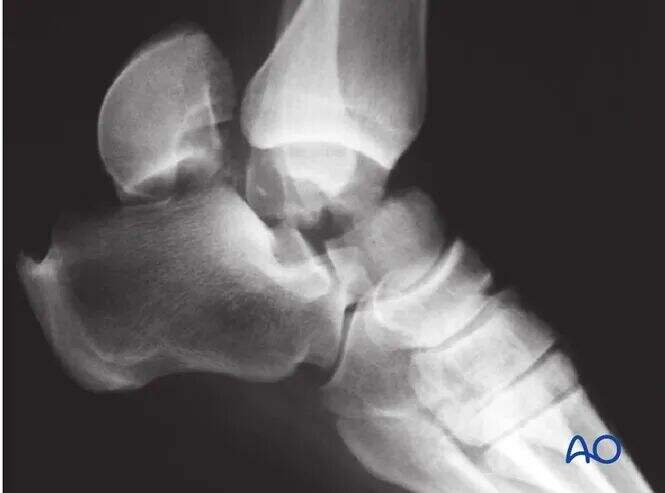

CT slikanje je neprecenljivo, kadar obstaja dvom o premiku zloma ali kadar je potrebno odstraniti okostnico subtalarne sklepa. Pri hujših poškodbah običajno velja, da večji premik nakazuje hujšo osteohondralno poškodbo subtalarne in tibiotalarne sklepa. Takšni zlomi pogosto zahtevajo kirurško odstranitev okostnice in fiksacijo.